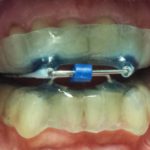

Update nella gestione del bite nei disordini temporo mandibolari Premium

In questo articolo viene presentato un protocollo nuovo e diverso di gestione del bite nei pazienti affetti da dolori neuromuscolari e disordini temporo mandibolari mediante un bite che coinvolge il paziente a effettuare esercizi orali attivi fisici, cognitivi e rieducativi per stimolare la riorganizzazione dinamico funzionale e probabilmente nel tempo anche la neuroplasticità cerebrale.